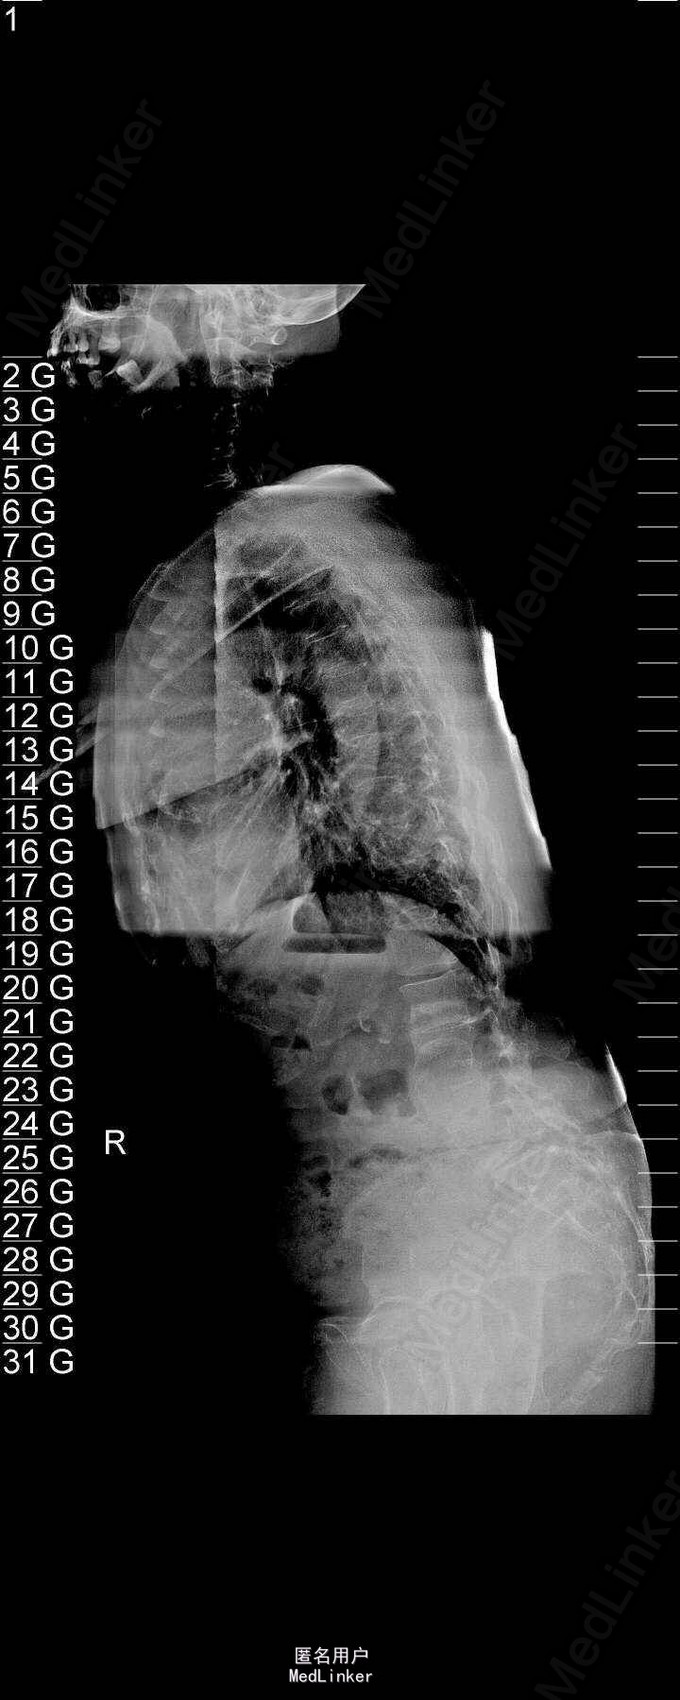

主诉:右下肢麻木伴驼背11年余 病史:患者女性,64岁,11年前无明显诱因出现右下肢疼痛,休息后好转。未予重视,后出现右下肢麻木感,逐渐小狐仙右臀部坚硬,驼背,伴跛行。常感双腿酸胀,腰部疼痛。自行步行距离小于200米,即会发生右下肢僵硬,麻木疼痛。X线检查示腰椎侧弯

查体:脊柱侧弯,上肢无麻木,疼痛感觉异常,腰部右侧疼痛,右下肢及右臀部疼痛,麻木感。双侧肌力及肌张力可,膝腱反射(+),踝反射(+),病理征(—),直腿抬高试验。右侧40度,左侧55度。 辅助检查:腰椎x线片:腰椎侧弯,腰椎退行性改变,L5椎体略行前滑脱 脊柱全长:胸腰段呈S形,L5椎体向前滑脱,L3椎体略变扁,颈胸腰椎退行性改变 MRI:脊柱侧弯,L2-3,L3-L4,L4-L5,L5-S1椎间盘突出,相应节段椎管狭窄

诊断:腰椎侧弯,腰椎椎管狭窄 治疗:手术矫形:早期侧路减压融合,后期再行后路固定。